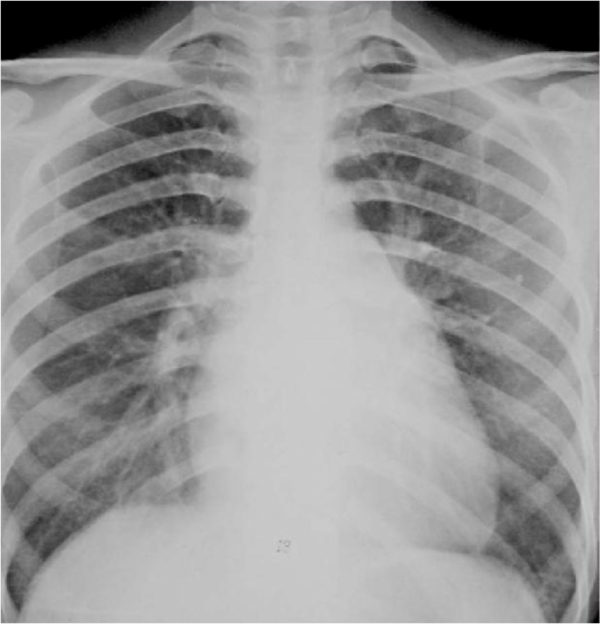

看图(扩张型心肌病,全心衰-心肌无力了)要么是心脏本身增大(心包积液

【求助】普大型心,梨形心,靴形心的片子究竟怎么看啊